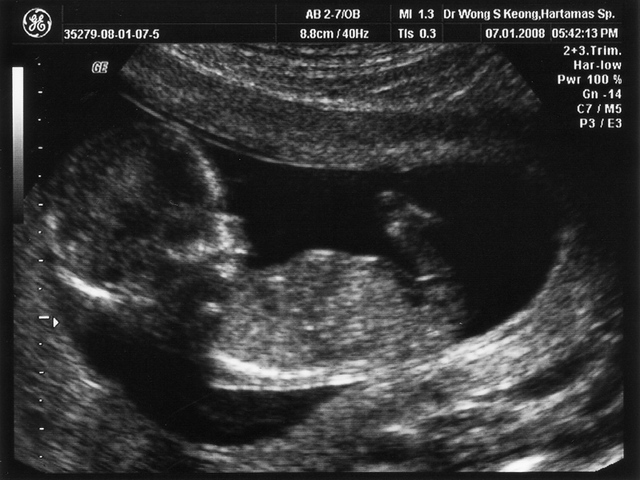

• Week Eight: First Prenatal Visit

Week Eight: First Prenatal Visit

The heart is beating around 150 beats per minute as the face begins to take shape. Limbs are still growing while eyes are developing.